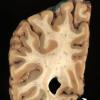

1A1 Striate cortex, normal (Case 1) Gross_2 copy

1A2 Striate cortex, normal (Case 1) Gross_3 copy